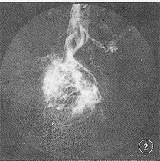

图2 右髂内动脉DSA造影显示肿瘤区大量的扭曲杂乱、粗细不均的新生肿瘤血管,肿瘤染色呈不规则团块状,可见血管湖及引流静脉早显